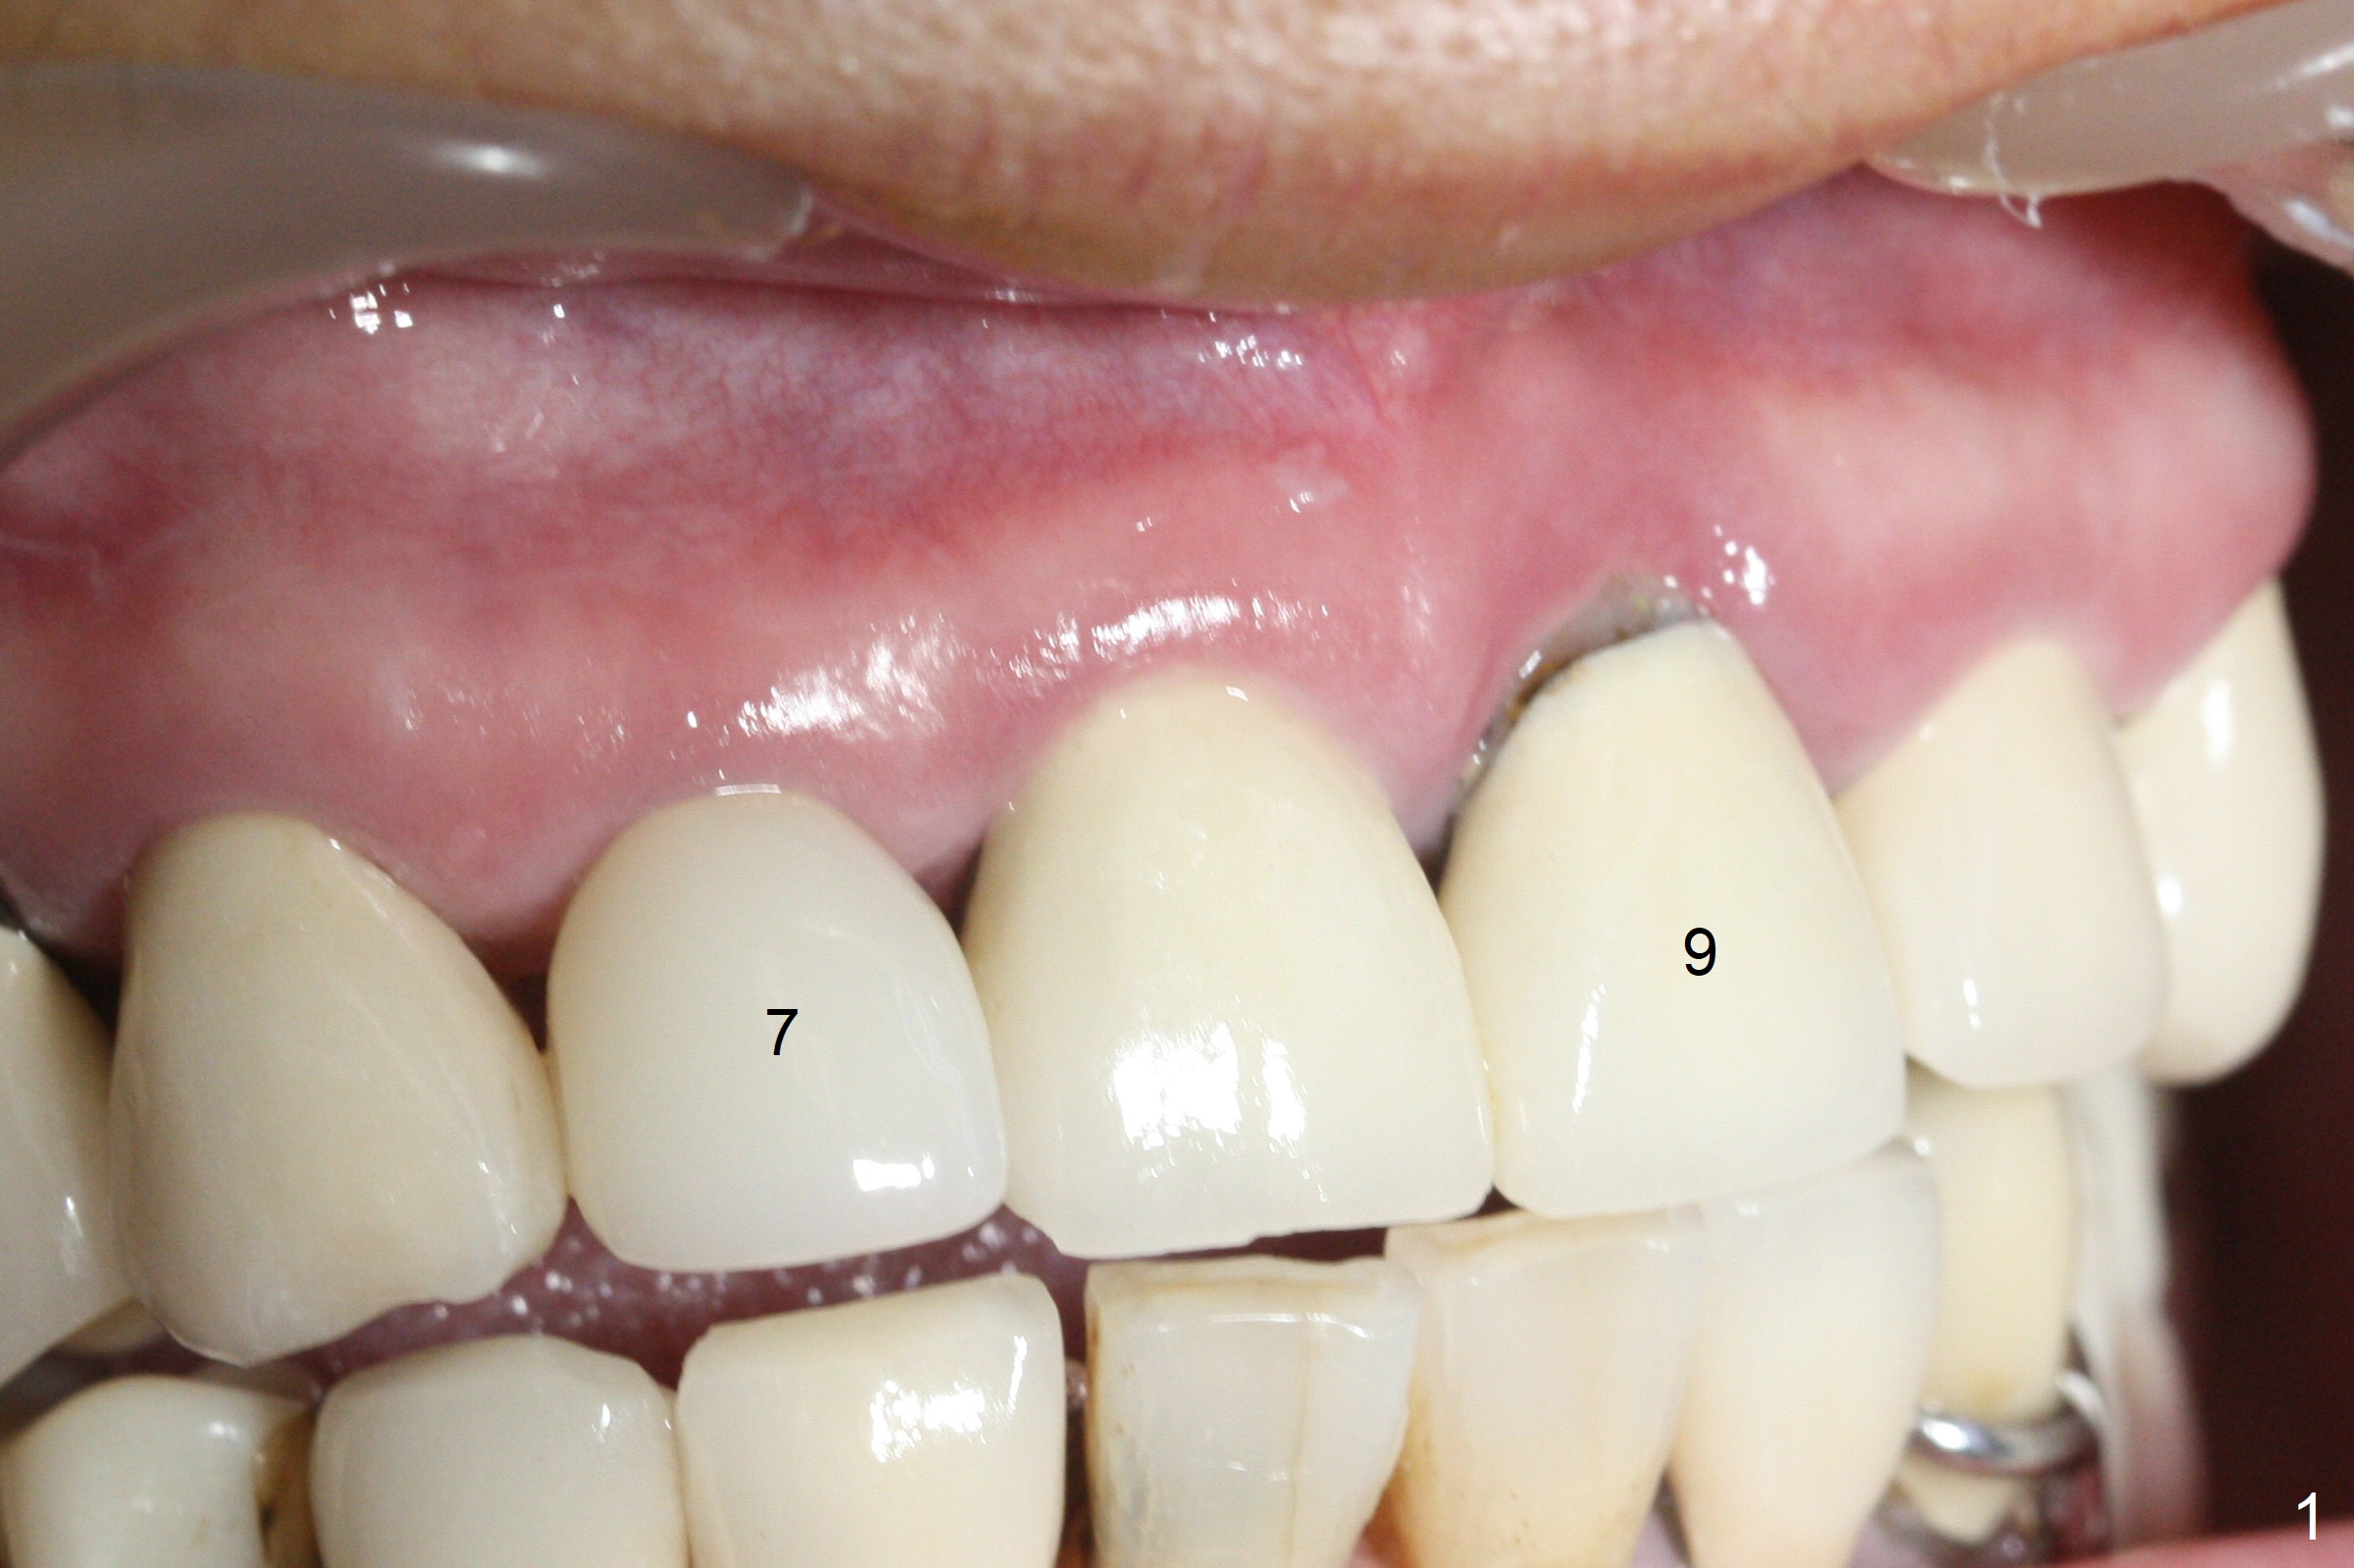

The buccal contour at #9 seems to be slightly concave preop (Fig.1,2 (*)). In fact the buccal plate is found to be lost when the tooth is extracted. Osteotomy is initiated as palatal as possible apical, but the occlusion dictates the coronal end of the osteotomy should be buccal, leaving the buccal gap ~ 2 mm for bone graft. The initial osteotomy (18 mm deep) appears to be close to the Incisive Foramen (Fig.3 blue dashed line). The nasal floor appears to be intact when the drill is removed. Subsequent osteotomy is adjusted so that the apical end of the osteotomy moves distal; when a 3.8x15 mm dummy implant is partially placed, there is clearance (Fig.4). It remains so when a definitive implant is seated (Fig.5); Vanilla graft is placed (Fig.5 *) before placement of a 4.5x5.5(3) mm abutment. More allograft is placed when an immediate provisional is fabricated (Fig.6 arrow and *). The gingiva remains to be recessive 1 month postop (Fig.7). It seems to be related to the bulky gingival margin of the provisional (Fig.8 *). After trimming the latter (Fig.9 *), the gingival margin immediately returns close to normal (Fig.10). The gingival margin is even between #8 and 9 two months postop, but the bone graft is exposed apically (Fig.11 ^). It may heals by itself. Otherwise debridement, regraft, PRF and suture are pending. The coronal portion of the socket heals 4 months postop (Fig.12). The gingival cuff forms by the immediate provisional (which is removed for impression) 4 months postop (Fig.13 *). While the full Zirconia crown at #7 remains intact (Fig.14), the PFM at #9 has porcelain chip (Fig.15). It is partially due to the occlusion; while the crown at #7 has clearance with the opposing dentition (Fig.16 *), the one at #9 has no. The access hole at #9 (Fig.17 *) seems to weaken the crown structure. There is no access hole at #7. No solid posterior support is another contributing factor for chip (Fig.18). The buccal plate has mild atrophy at #7 and 9 (Fig.19 *). A piece of bone graft is being expelled apically at #9 (Fig.20 >) and is removed subsequently (Fig.21). Before impression for repacking porcelain, the opposing incisal edge has been shortened (Fig.22 arrows, as compared to Fig.16). Since the ideal access hole is at the incisal edge (Fig.25 black circle), buccal to the existing one (Fig.24 A), the abutment is torqued before the repaired crown is recemented (Fig.23). Finally the crown has occlusal clearance (Fig.26). Porcelain chips again around the access hole of PFM 1.5 years post 2nd cementation. The dense bone at the crest (*) cannot explain why the abutment is not loose, since it remains incompletely seated (>). As it was trimmed short, an angled abutment is used (Fig.28). The coronal end is lingual, while #9/24 is edge to edge. The lingual aspect of the coronal end of the abutment is heavily trimmed to reduce bulkiness. To prevent chip, Zirconium crown will be fabricated in spite of the fact that it does not match the PFM of #8 (potential shade discrepancy). The patient is pleased with the new Zirconia crown (Fig.29).